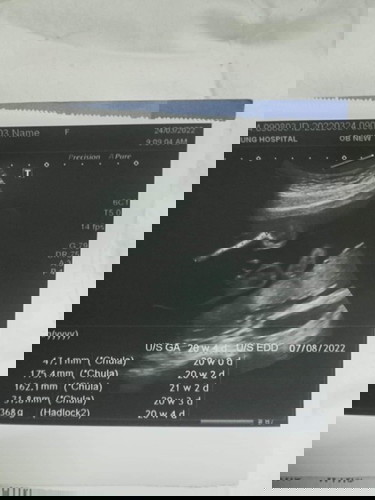

อยากรู้ว่าน้องน้ำหนักน้อยเกินไปไหมคะ

ตอนนี้น้องได้ 20 สัปดาห์ 4 วันแล้ว 368 กรัม